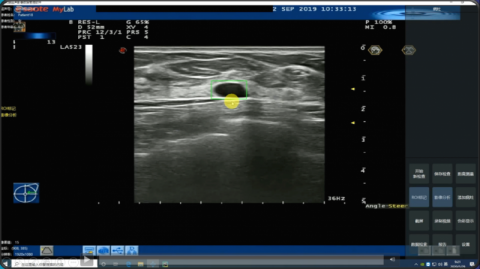

医准智能乳腺超声智能检测系统界面

日前 , 北青-北京头条记者来到医准智能的研发办公区 , 技术人员演示起刚刚推出的技术产品——乳腺超声智能检测系统 。 超声探头放在病人身体的扫查区 , 屏幕中的超声影像不断闪现 , 医生只需点击标记按钮 , 屏幕上立刻出现一个矩形框 , 勾画出病灶区 , 供医生进一步判别 。 随着探头轻微变换角度 , 矩形框也随着视频图像信息变动即时调整 。

目前 , 乳腺超声智能检测系统已完成科研攻关 , 近期该系统将在全国十余家三甲医院临床试用 。 北青-北京头条记者了解到 , 该系统具有计算速度快、病灶识别检出率高、误报率低等优势 , 可实现每秒处理速度超50帧 , 且检测结果延迟小于0.09秒 。 在检测过程中 , 可自动测量病灶最大截面等定量信息 , 并自动生成诊断报告 。